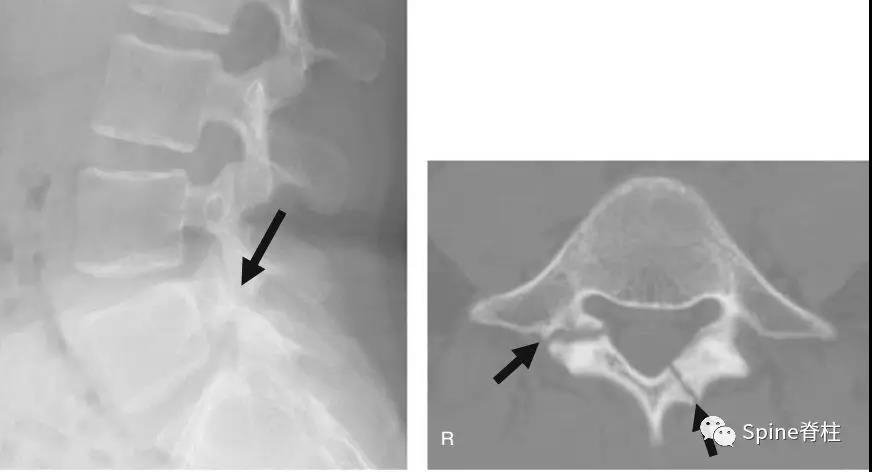

椎弓根螺钉“断钉”取出技巧,全都整理好了!

椎间融合手术对于后期脊柱稳定起到至关重要的作用。那么后期植骨不愈合,导致后期椎弓根螺钉“断钉”的几率会高很多,临床中取出“断钉”还是有不少困难的,下面分享几种“断钉”的应对方法